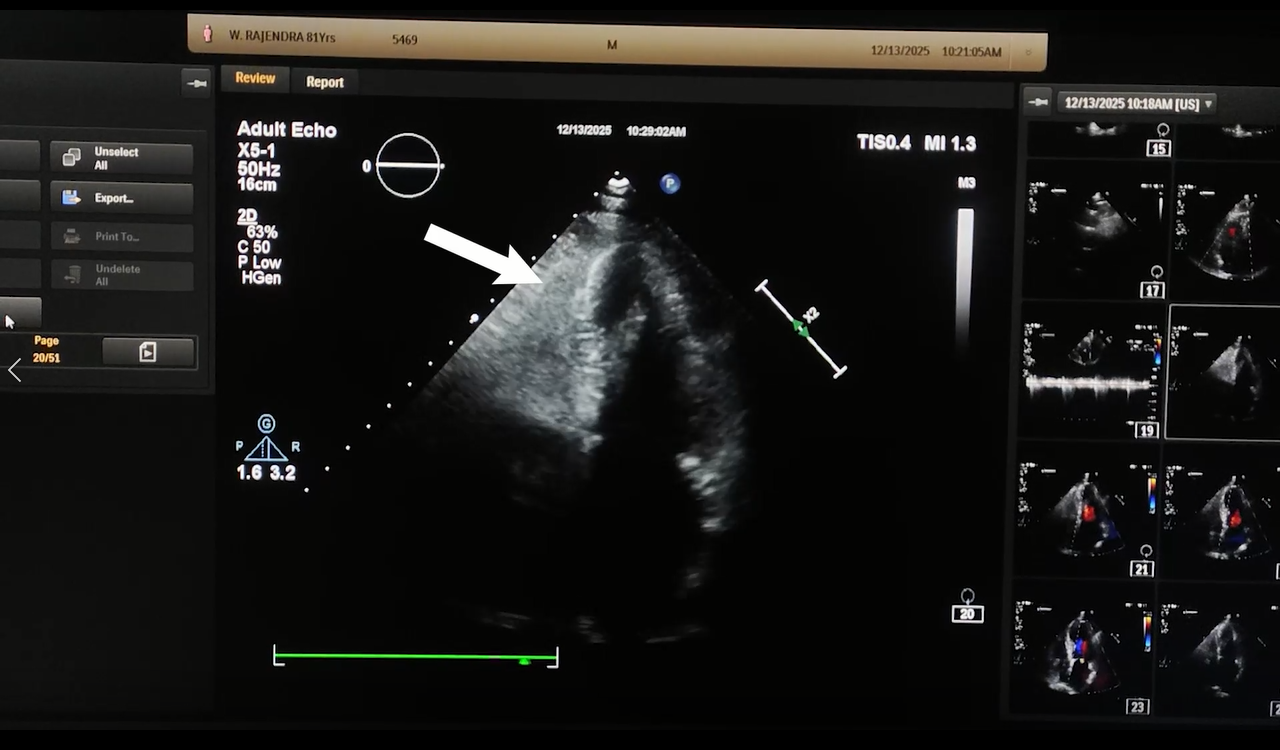

The ECG at 7-month follow up after discharge showed near normalization of T-waves and ST-segment in iso-electric line. Echocardiogram done on the same day showed improved LVEF at 53.4%. At 9-month follow up, the ECG showed normalization of T-waves (Figure. 1c, marked with arrow head) and ST-segment in iso-electric line. Echocardiogram on the same day showed normalization of LVEF at 56.9% (Figure 2b).

Figure 2(b): Echocardiogram performed at 9-month follow up showed normalization of LVEF (56.9%).